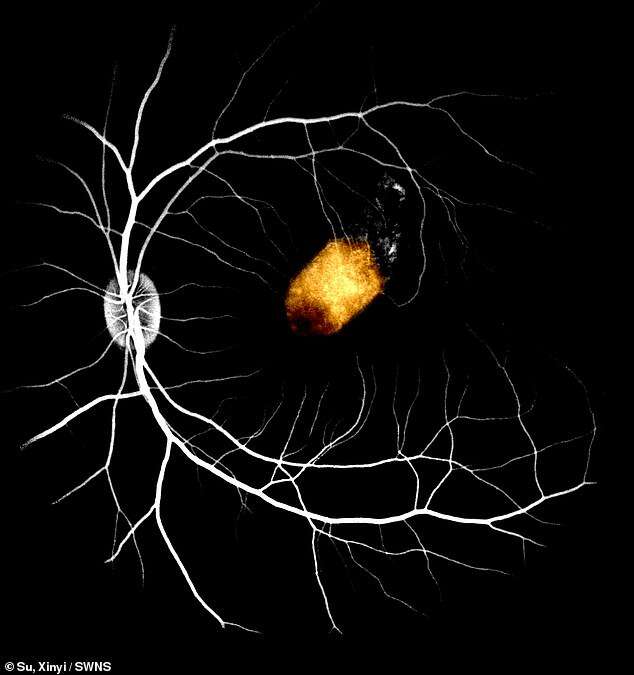

Artykuł dostępny w Stem Cell Reports sugeruje, że naukowcy z Chin przeszczepili komórki macierzyste siatkówki pobrane z ludzkich zwłok, umieszczając je następnie w oczach małp. W efekcie wykształciła się u nich tzw. warstwa barwnikowa siatkówki.

Ta warstwa, zwana również częścią barwnikową siatkówki, umożliwia m.in. pochłanianie rozproszonego światła i jest niezbędna do prawidłowego widzenia. Idąc w drugą stroną, nieprawidłowe funkcjonowanie lub całkowity brak wspomnianej warstwy stanowi główną przyczynę ślepoty.

Na przykład zwyrodnienie plamki żółtej dotyka około 200 milionów ludzi na całym świecie. Nadzieją dla takich osób może być terapia opracowana przez chińskich badaczy. Autorzy badań twierdzą, że komórki mogłyby być pobierane z ludzkich zwłok, a następnie przeszczepiane. Taka metoda dawałaby możliwość ratowania wzroku u pacjentów z chorobami siatkówki.